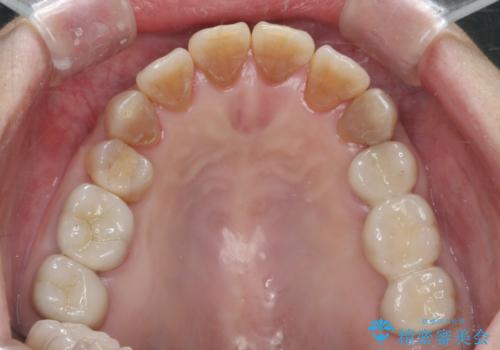

においやぐらつきなどの深い症状がなくなり、しっかりと噛めるようになった!と喜んでいただくことができました。